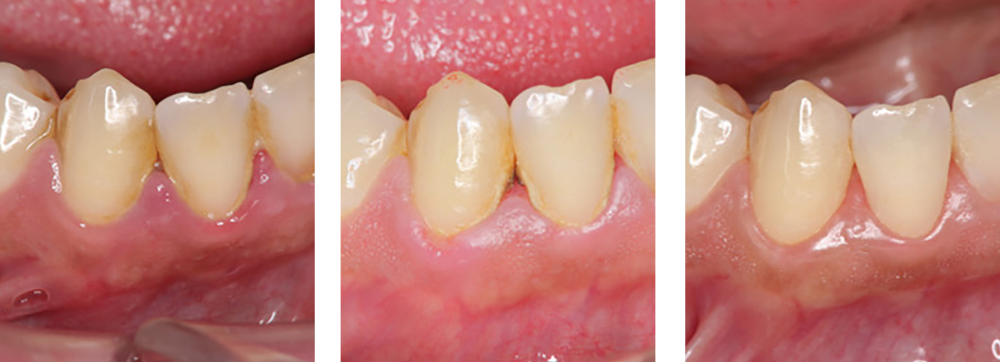

歯周病治療

術前

術中

術後

| 治療内容 | 歯磨き指導を行い、歯肉の発赤・腫脹が改善されたため歯石除去を行った |

|---|---|

| 治療期間・回数 | 2カ月・3回 |

| 費用 | 保険適用となります |

| リスク・副作用 |

|